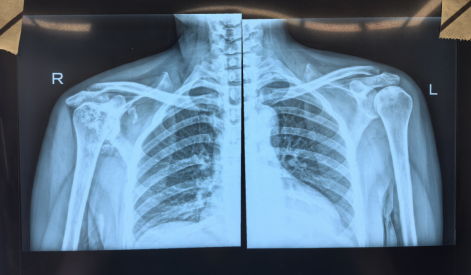

患者术前DR

入院后,尹宗生、陆鸣带领团队对郭女士的病情进行了仔细分析,若要从根本上解决问题只能进行人工反式肩关节置换术治疗。在同患者及其家属进行沟通并取得同意后,最终决定为其实施右侧人工反式肩关节置换术。术后恢复良好,右肩关节功能明显改善,目前正在积极功能康复锻炼中。